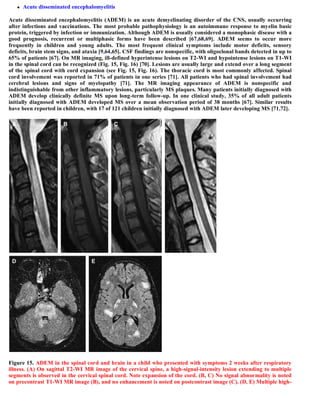

This document discusses a case of spinal multiple sclerosis in a 40-year-old patient. MRI images show well-defined pencil-shaped lesions occupying 2-3 spinal segments that are hypointense on T1-weighted images and hyperintense on T2-weighted images. Diffuse abnormalities are also seen as poorly demarcated hyperintense regions on T2-weighted images. The diagnosis is spinal multiple sclerosis. The document then discusses features of spinal MS lesions seen on MRI such as focal lesions, diffuse abnormalities, and spinal cord atrophy, and compares features of MS to other conditions like neuromyelitis optica.